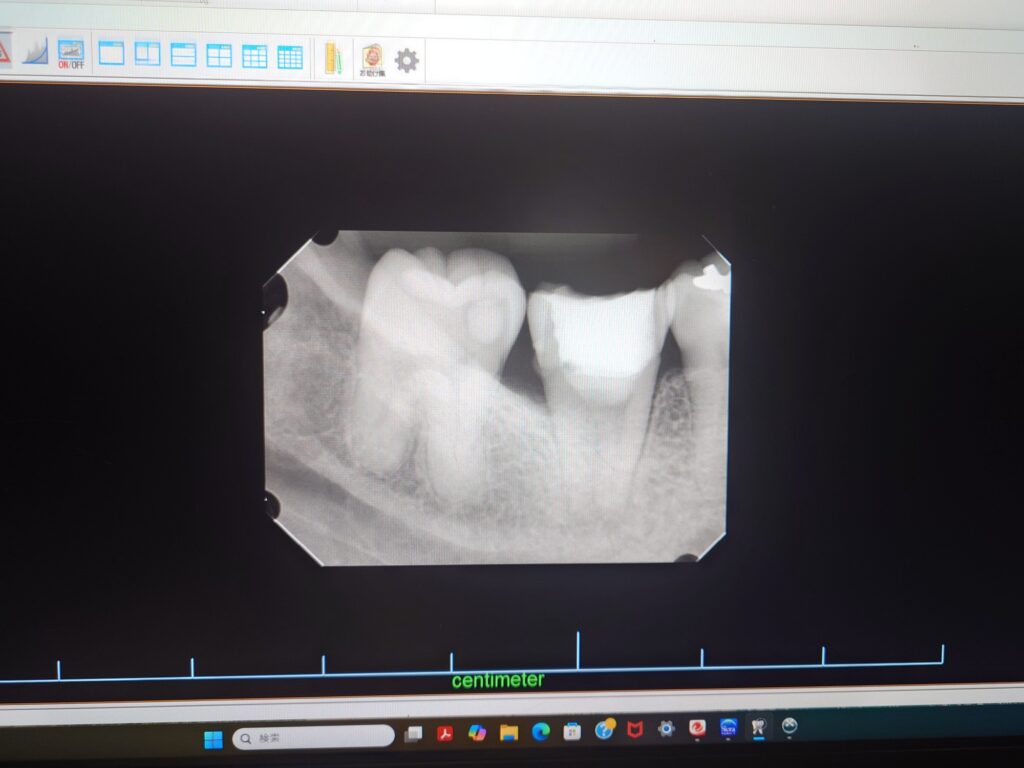

患者さん本人の歯髄幹細胞を移植した後のレントゲンです

ここまで来るのになかなか根の中の無菌化ができず苦労しました。

徹底的な滅菌と設備、米国歯内療法専門医による確かな技術によりようやく無菌化できました

これから1~2か月歯髄ができるのを待ちます

歯髄を再生することで 歯の強度は上がります

歯根破折のリスクもなくなることが期待できます